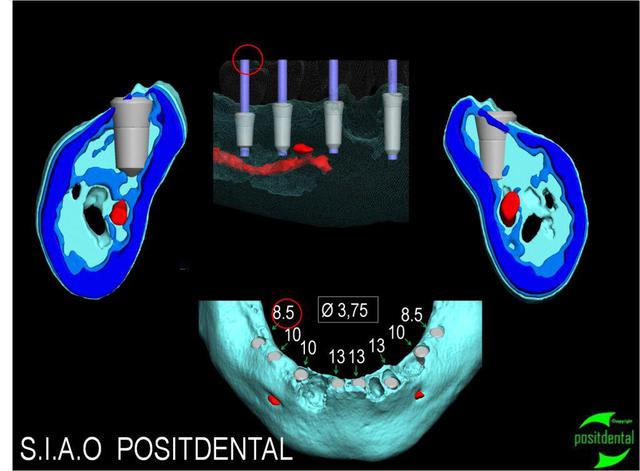

rapport entre les implants, le N.A.I et l'artère sublinguale.

Détails en coupes.

pourquoi ne pas mettre 5 implants entre les foramen mentonniers ( 1 central, 2 en avant des foramen et 1 entre l'implant central et distal de chaque côté) ?

Ben parce qu'il y a en pas mal en postérieur, aussi, il y a des défauts osseux. Pour en placer 5, un nivellement important de la crête en verticale serait requis.

Ceci dit, je place souvent 5 entres les foramens, en applanissement la crête. Mais souvent, il n'y a pas des place en postérieur, ici semble que oui, avec un total de 8 implants.